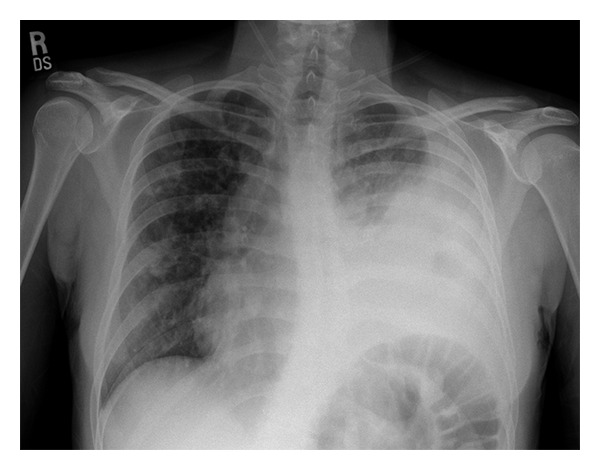

Input 3: What is seen in the X-ray and what should be done?

Image:

- Visual Med-Alpaca: Bilateral infiltrates and bilateral pleural effusion seen in a chest x-ray may indicate a respiratory infection or other respiratory conditions such as pneumonia pulmonary edema, or pleural effusion, it is important to consult a medical professional for a proper diagnosis and treatment plan.

- VQA Medical Model: the decubitus

- Automatic Radiology Report Generation (Image-only): near complete opacification of the left hemi thorax with only a small amount of residual aerated lung in the left upper lobe .

- ChatGPT (GPT-3.5-Turbo) + Automatic Radiology Report Generation (Image-only): Opacification of the lung on an X-ray indicates that there is an abnormality in the lung tissue. In this case, the near-complete opacification of the left hemithorax with only a small amount of residual aerated lung in the left upper lobe suggests that there is likely a significant pathology present in the left lung. Possible causes of this finding include pneumonia, lung abscess, tumor or mass, or pleural effusion (fluid accumulation around the lung). It is important to determine the underlying cause of this finding as soon as possible. A follow-up diagnostic workup may include a CT scan of the chest, sputum culture, bronchoscopy, and/or a biopsy of any suspicious areas in the lung. The appropriate treatment will depend on the underlying cause, but it may include antibiotics, drainage of any fluid collections, or surgery to remove any masses or tumors. Prompt evaluation and treatment are necessary to prevent complications and improve outcomes.